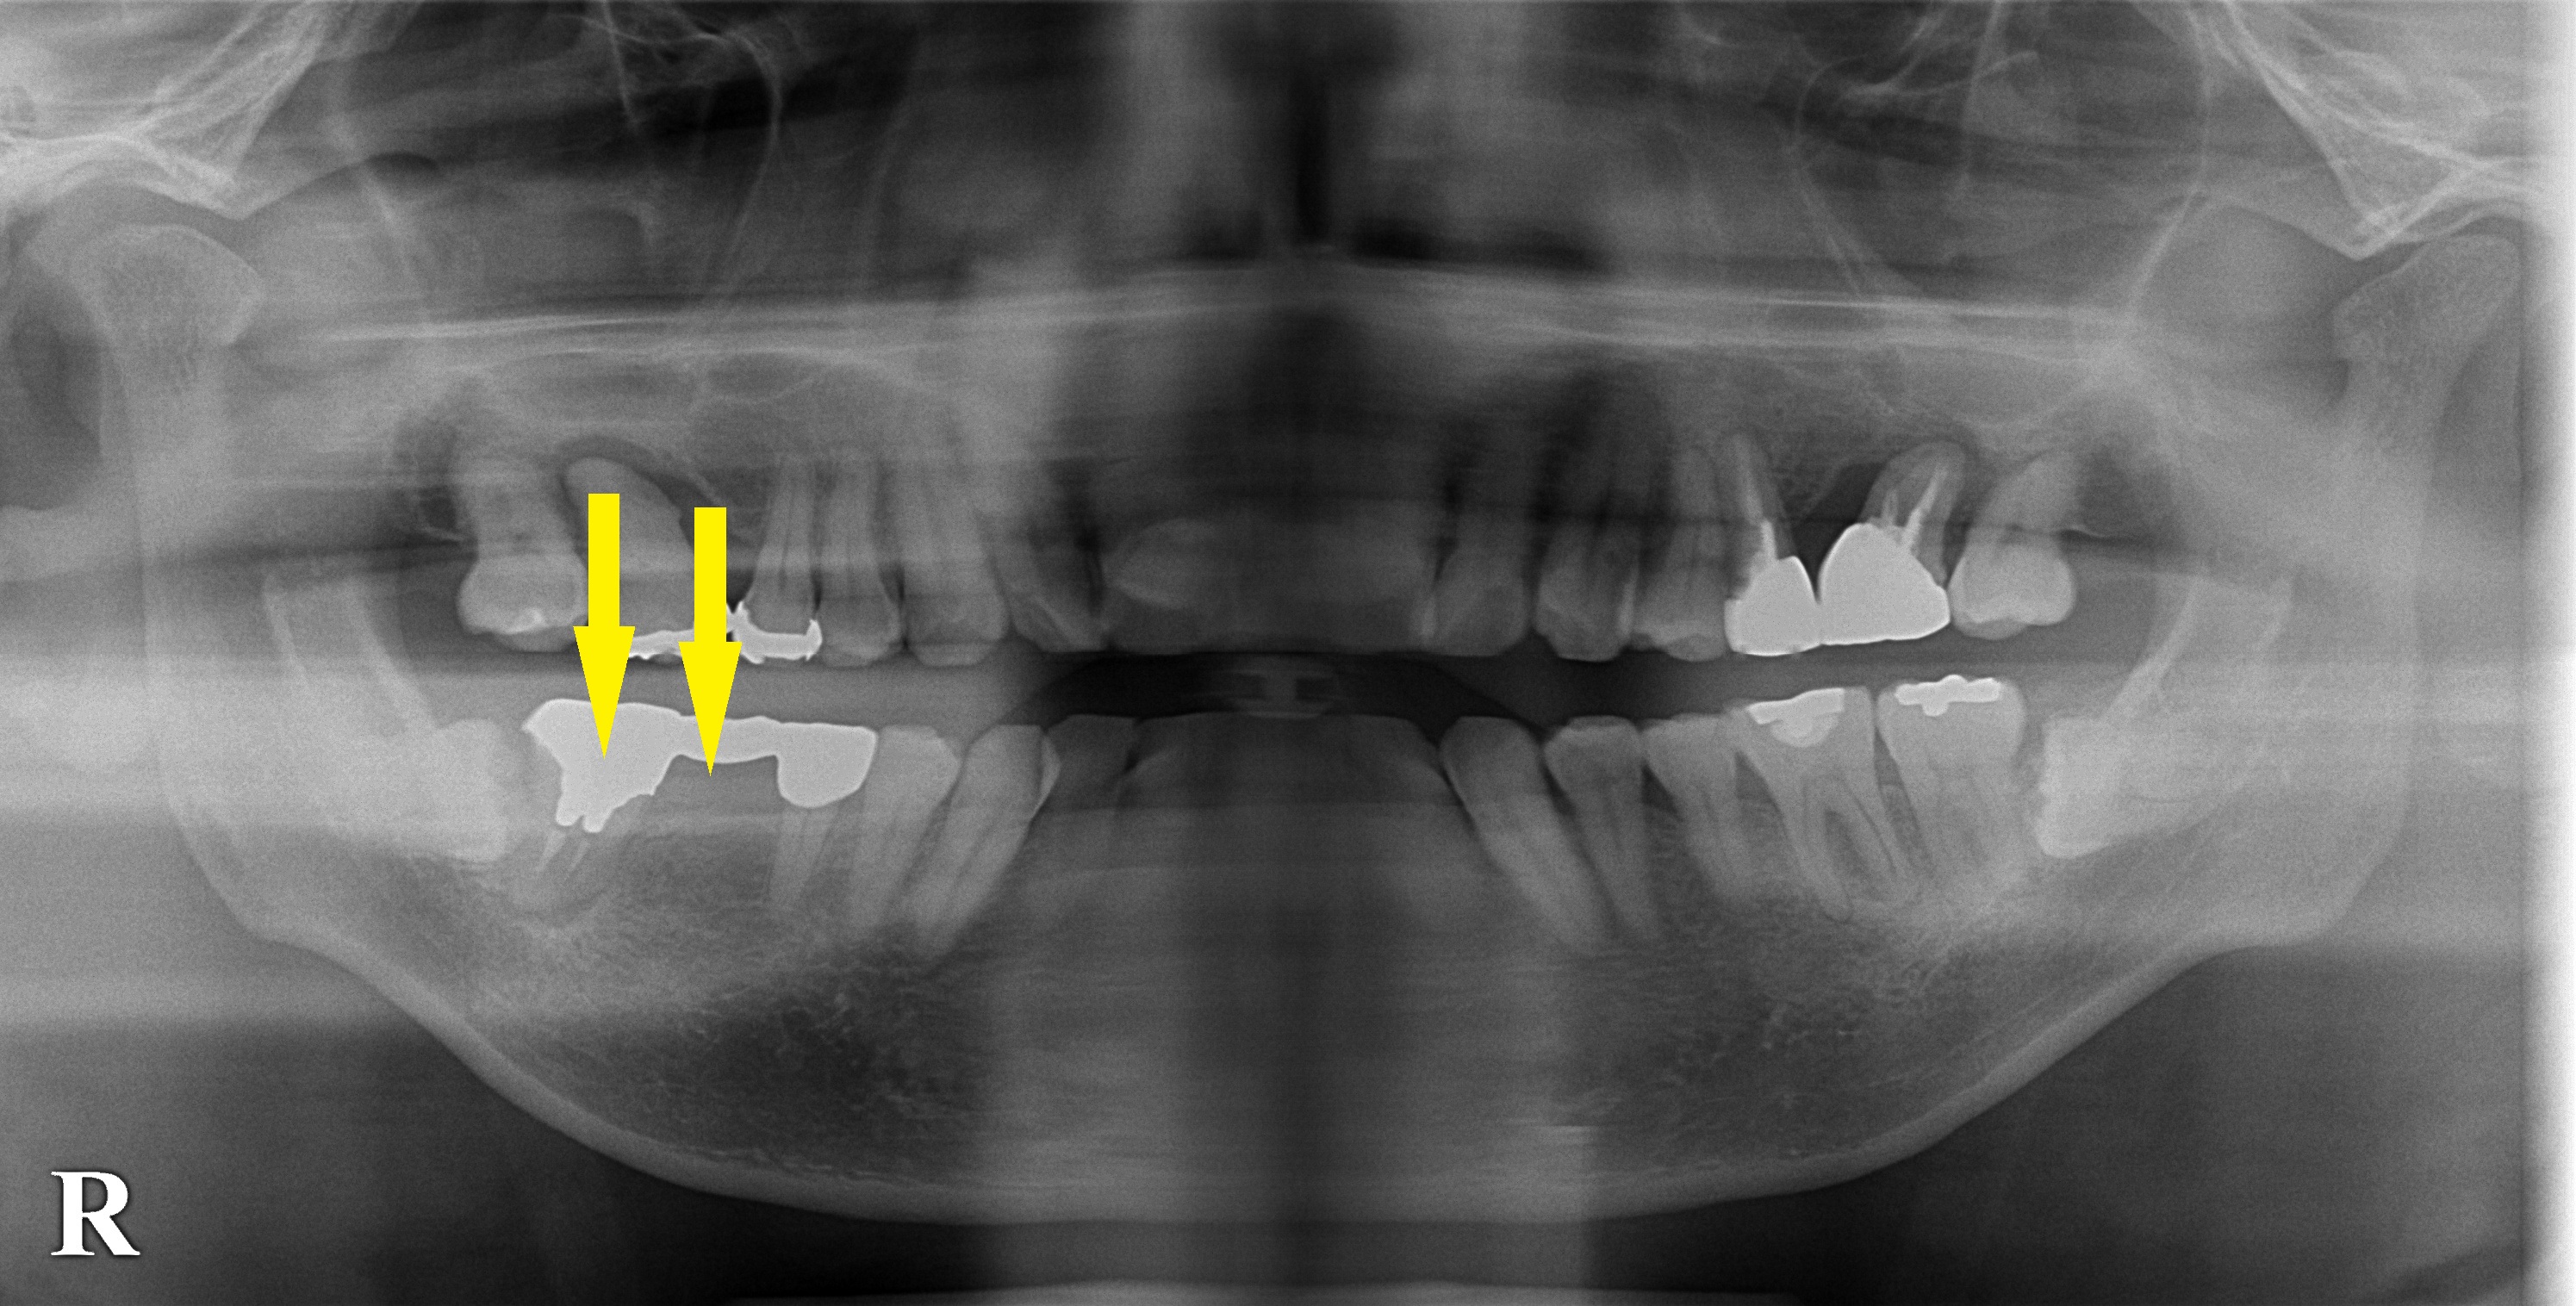

了承いただけましたので、5か月前に自家骨移植術を行ない、本日インプラント埋入術を行ないました。

移植した骨は周囲骨と一体化して生着しており(下段右写真、真っ白に写っているのは骨を固定したマイクロスクリュー)、良好なインプラント埋入が可能でした。